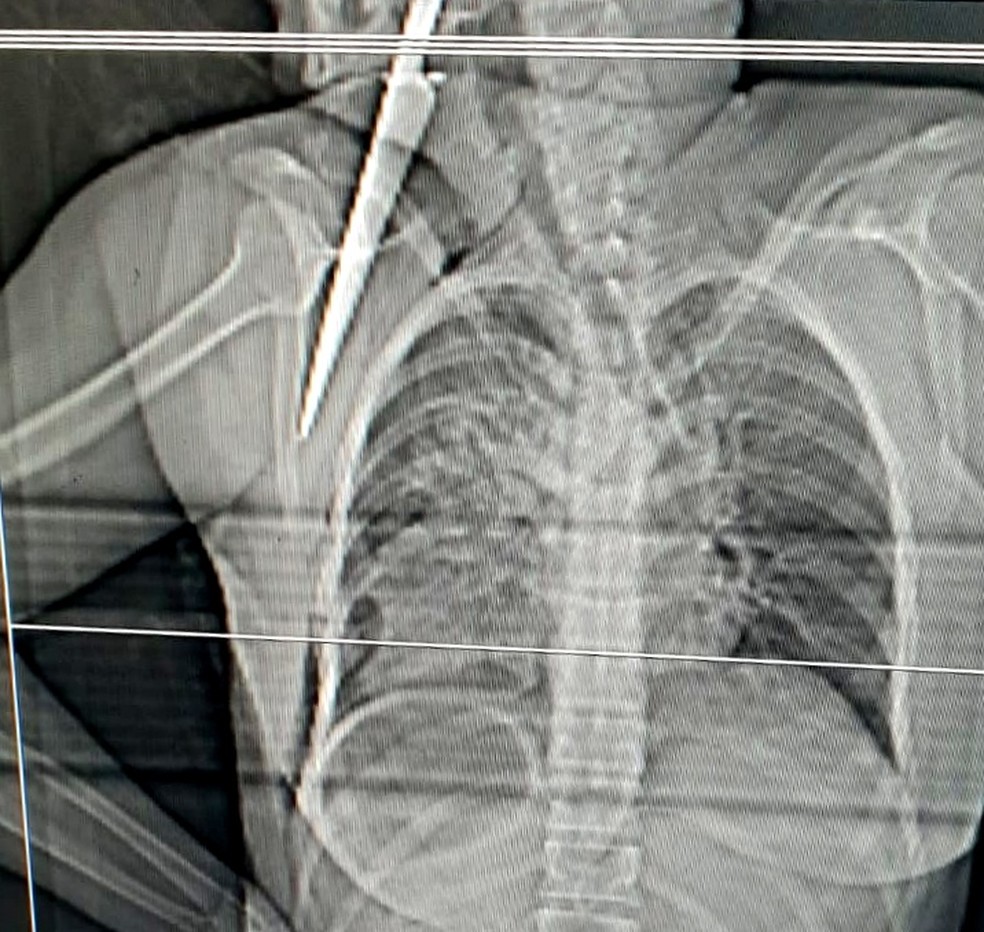

Imagens de raio-x mostram a lâmina de 20 cm presa na vítima. Crime aconteceu porque o autor das facadas não aceitava o fim do relacionamento. Ela foi operada para a remoção do objeto e o quadro de saúde é estável.

Faca fica cravada no tórax de mulher após ataque do ex, no ES — Foto: Reprodução

Uma mulher foi esfaqueada pelo ex-companheiro, na tarde desta terça-feira (8), em Pinheiros, no Norte do Espírito Santo. A faca ficou cravada no corpo da vítima.

Segundo a Polícia Civil, a mulher de 45 anos estava em casa quando o homem chegou e tentou reatar o relacionamento deles. Ela foi operada para a remoção do objeto e o quadro de saúde é estável.

Diante da negativa da vítima, o homem deu três facadas na vítima. No último golpe, a lâmina da faca, de 20 cm de comprimento, ficou presa no corpo da mulher.

Os golpes atingiram os dois pulmões e fraturaram a escápula da vítima, onde a faca ficou cravada.